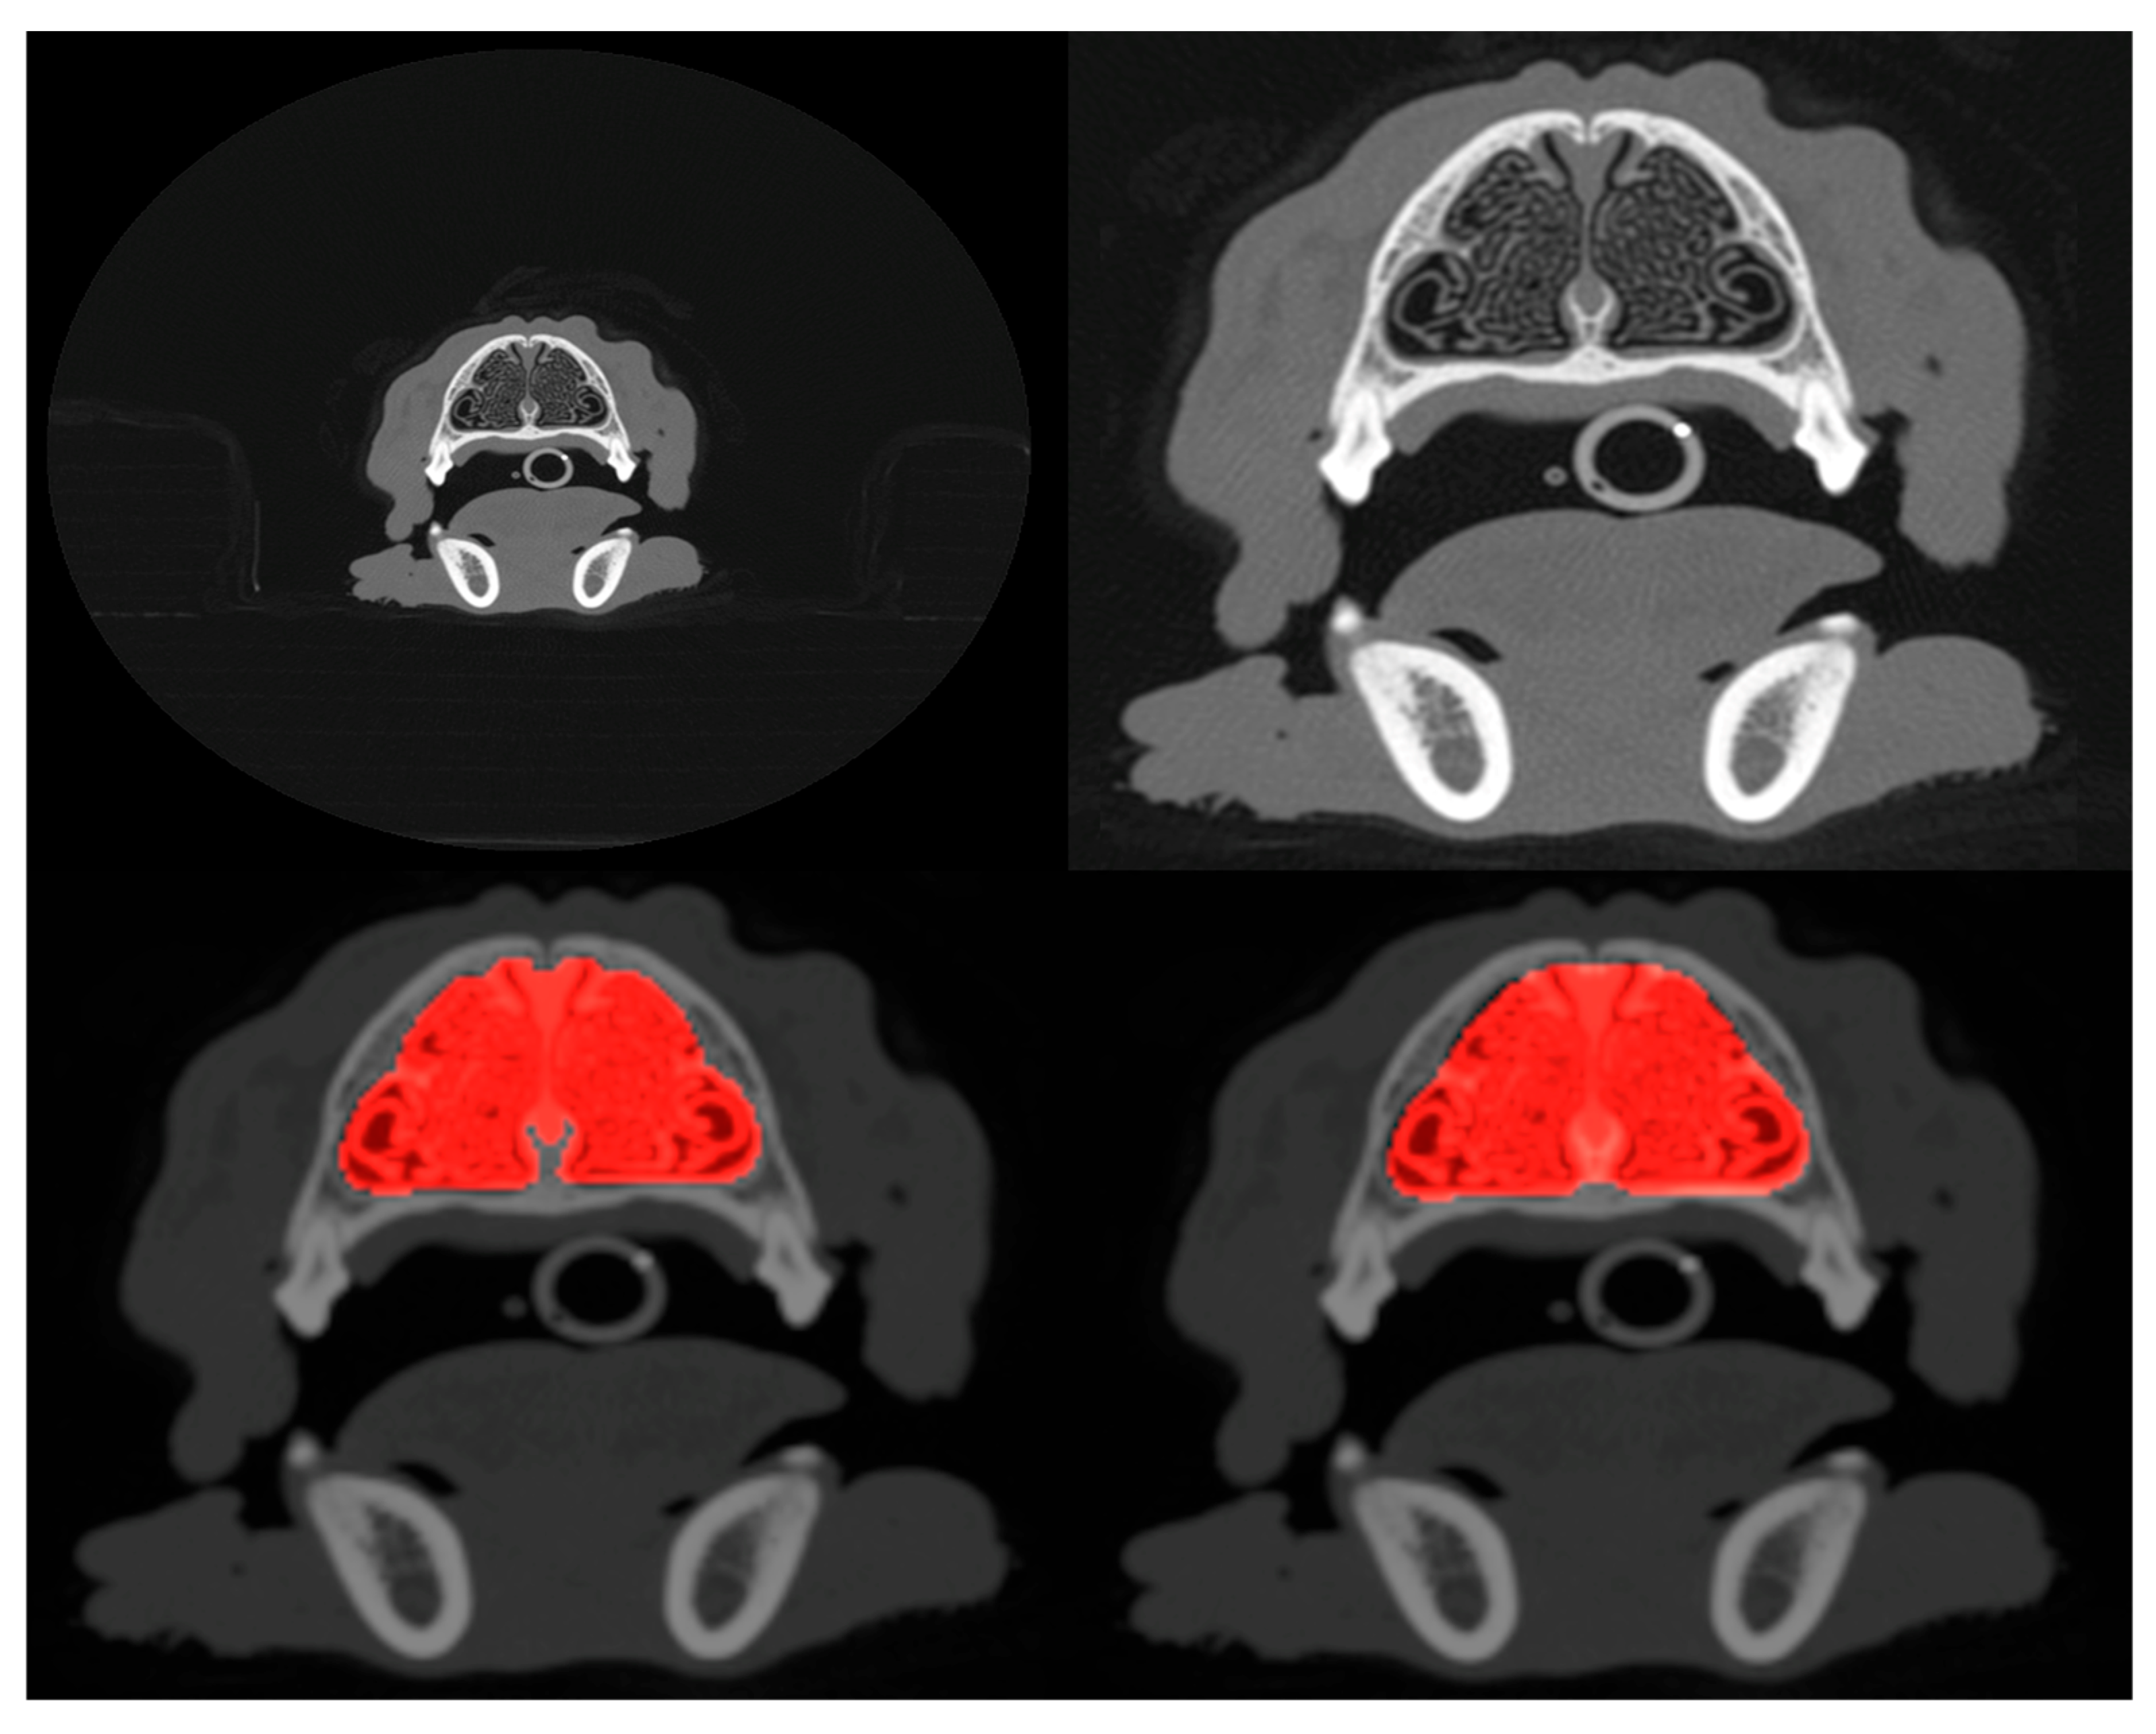

3. Results

The metrics corresponding to the CNN model applied to both cropped and uncropped test slices with image dimensions of 96 × 96 pixels are shown in Table 1. The accuracy of identifying slices containing a nasal cavity with the uncropped scans is 96.2 percent with a standard deviation of 2 percent estimated from the 5-fold cross-validation. Out of typically 150 slices per patient intersecting the nasal cavity, this corresponds to only ~6 being misidentified on average. When applied to the cropped scans, the CNN exhibits a slight degradation in performance corresponding to a mean misidentification rate of ~8 slices per patient. Figure 2 (left panel) shows the validation loss and accuracy curves for the slice extraction model. Some example slices rejected and selected by the model are shown in Figure 3.

Figure 3. Example slices rejected (left) and accepted (right) by the model as intersecting the nasal cavity in one patient.